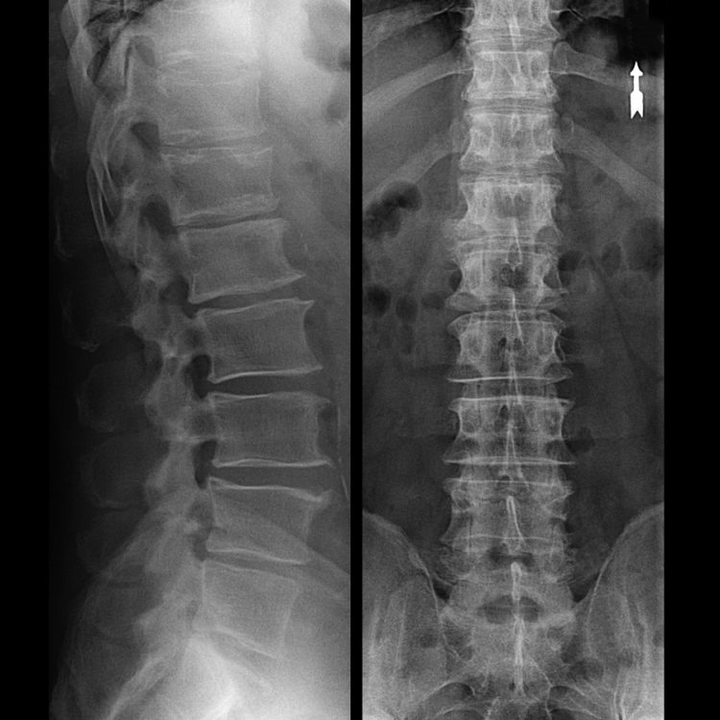

osteochondrosis of the vertebral region on x-ray

"X-ray" of the cervical spine, and even with functional flexion and extension tests, does not show cartilage, since its tissue transmits X-rays. Despite this, based on the location of the vertebrae, general conclusions can be drawn about the height of the intervertebral discs, the general straightening of the physiological curvature of the neck - lordosis, as well as the presence of marginal growths on the vertebrae with prolonged irritation of their surfaces by fragile and dehydrated intervertebral discs.Functional tests can confirm the diagnosis of cervical spine instability.

• You can regularly have at least an x-ray of the lumbar spine in two projections, or an MRI, to know whether the hernia, if any, is progressing;